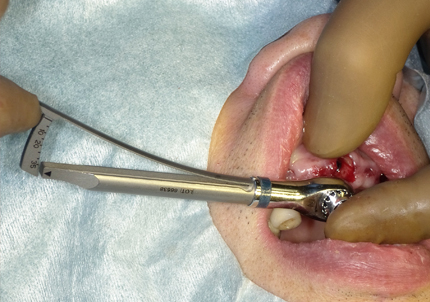

11.舌側歯牙片の抜歯

【右上1番SST 口蓋側歯根の抜歯】

【左上2番 SST 口蓋側歯根の抜歯】